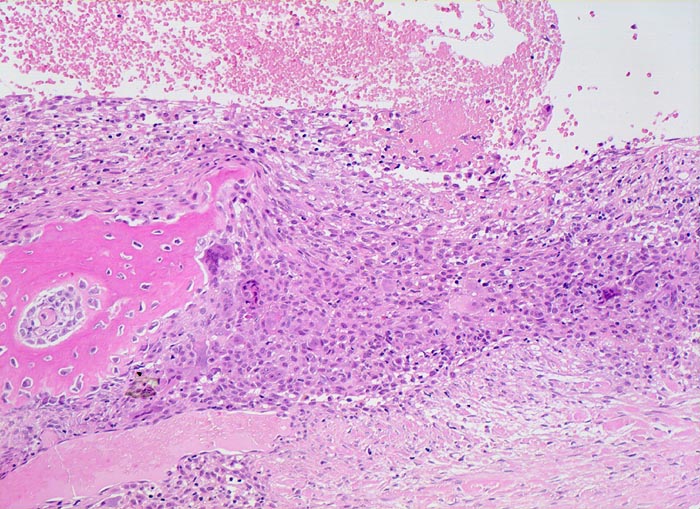

aneurysmatische Knochenzyste (AKZ)

Knochen, Fibula

Pseudozystischer Hohlraum ohne Epithelauskleidung gefüllt mit Blut. Die Pseuozystenwand enthält Riesenzellen und mononukleäre Zellen angrenzend an zellarmes kollagenes Bindegewebe. Daneben sieht man neugebildeten Faserknochen.

Lokalisierte Schmerzen und Schwellung in der proximalen Fibula. Im Röntgenbild ist eine Osteolyse erkennbar, die die betroffene Fibula auftreibt. Die Cortikalis über der Osteolyse ist hauchdünn.